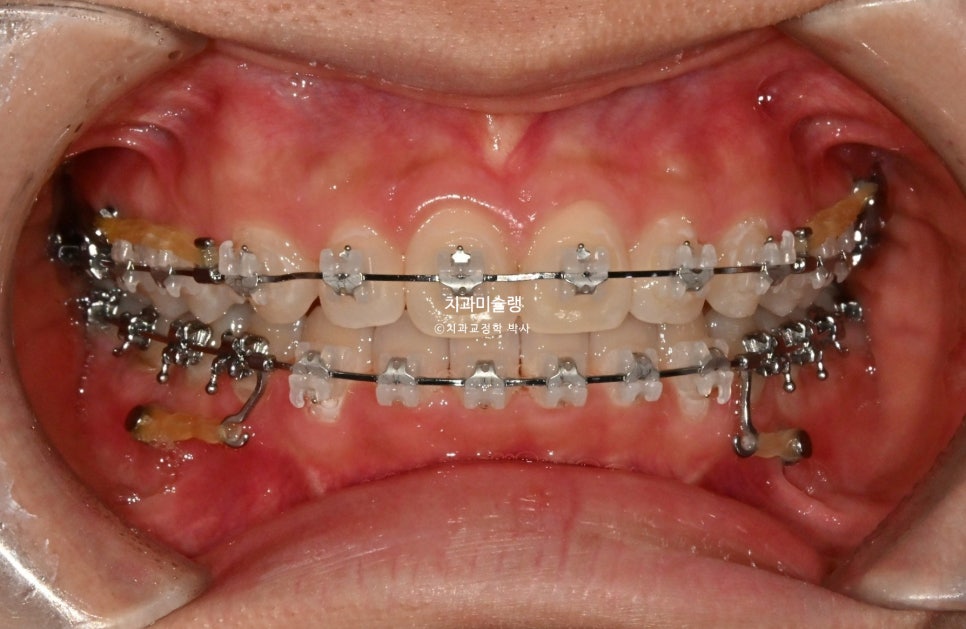

치료 시작 1년차 모습입니다. 치료 도중 턱관절 불편감은 딱히 없었습니다.

인비절라인에서 클리피씨로 바꿨기 때문에 턱관절이 편해진건 아닙니다.

앞니 과개교합으로 인한 조기접촉을 초기에 먼저 해결했기 때문이죠.

고정용 나사를 4군데 심고 전체치열을 뒤로 당기고 있습니다.